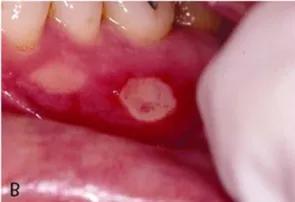

口腔内壁糜烂,口腔内壁溃烂

总有一些人会出现嘴巴疼痛和口臭,患者口腔内常出现白色的糜烂部位

为口腔内舌边,上颚,口颊,齿龈等处发生溃疡,周围红肿作痛,溃面糜烂

口腔粘膜溃烂·脱落

口腔内壁溃烂

口腔糜烂

口腔糜烂严重

口腔糜烂图片

口腔糜烂症状图片

口腔溃疡糜烂图片